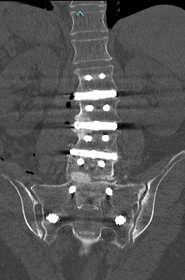

術前MRIでは腰椎正面で弯曲を認めています。多椎間の脊椎固定術を施行し症状が改善しています。

変性側弯症の患者さんで、難治性の腰痛と夜間も続く坐骨神経痛のために日常生活が困難でした。下位腰仙椎の多椎間で変性、側弯変形を認めます。

腰仙椎前方後方同時固定術による側弯変形の矯正、神経の除圧を行いました。悩んでいた腰痛がなくなり、坐骨神経痛が無くなったため夜間も穏やかに眠れるようになりました。